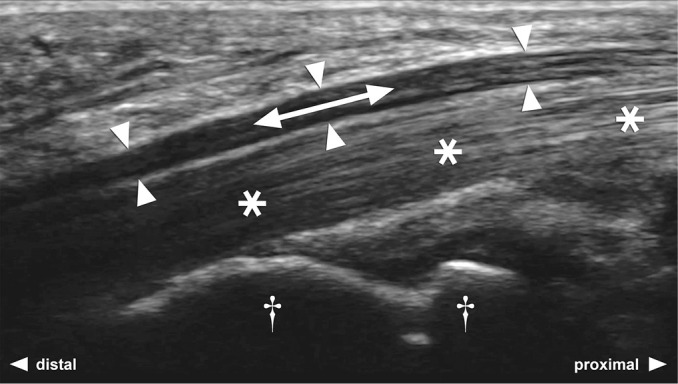

Methods: Longitudinal gliding of the median nerve in the carpal tunnel was visualized in all patients with idiopathic CTS and healthy controls. All ultrasound videos were pseudonymized, equipped with a scale, and randomized. Videos were analyzed by four independent radiologists, all blinded to clinical characteristics. The endpoint was gliding rated as millimeters. Validity of the technique was tested by using speckle tracking software, and in body donors, directly measuring nerve excursion in situ, simultaneously to ultrasound.

Results: Gliding differed significantly between controls and patients with CTS, decreasing with incremental CTS severity. A cut-off value of 3.5 mm to identify patients with CTS, yielded 93.8% sensitivity and 93.3% specificity. Intraclass correlation coefficient among senior author and raters was 0.798 (95% CI 0.513 to 0.900, P<0.001), indicating good reliability. Speckle tracking and especially direct validation in body donors correlated well with ultrasound findings.